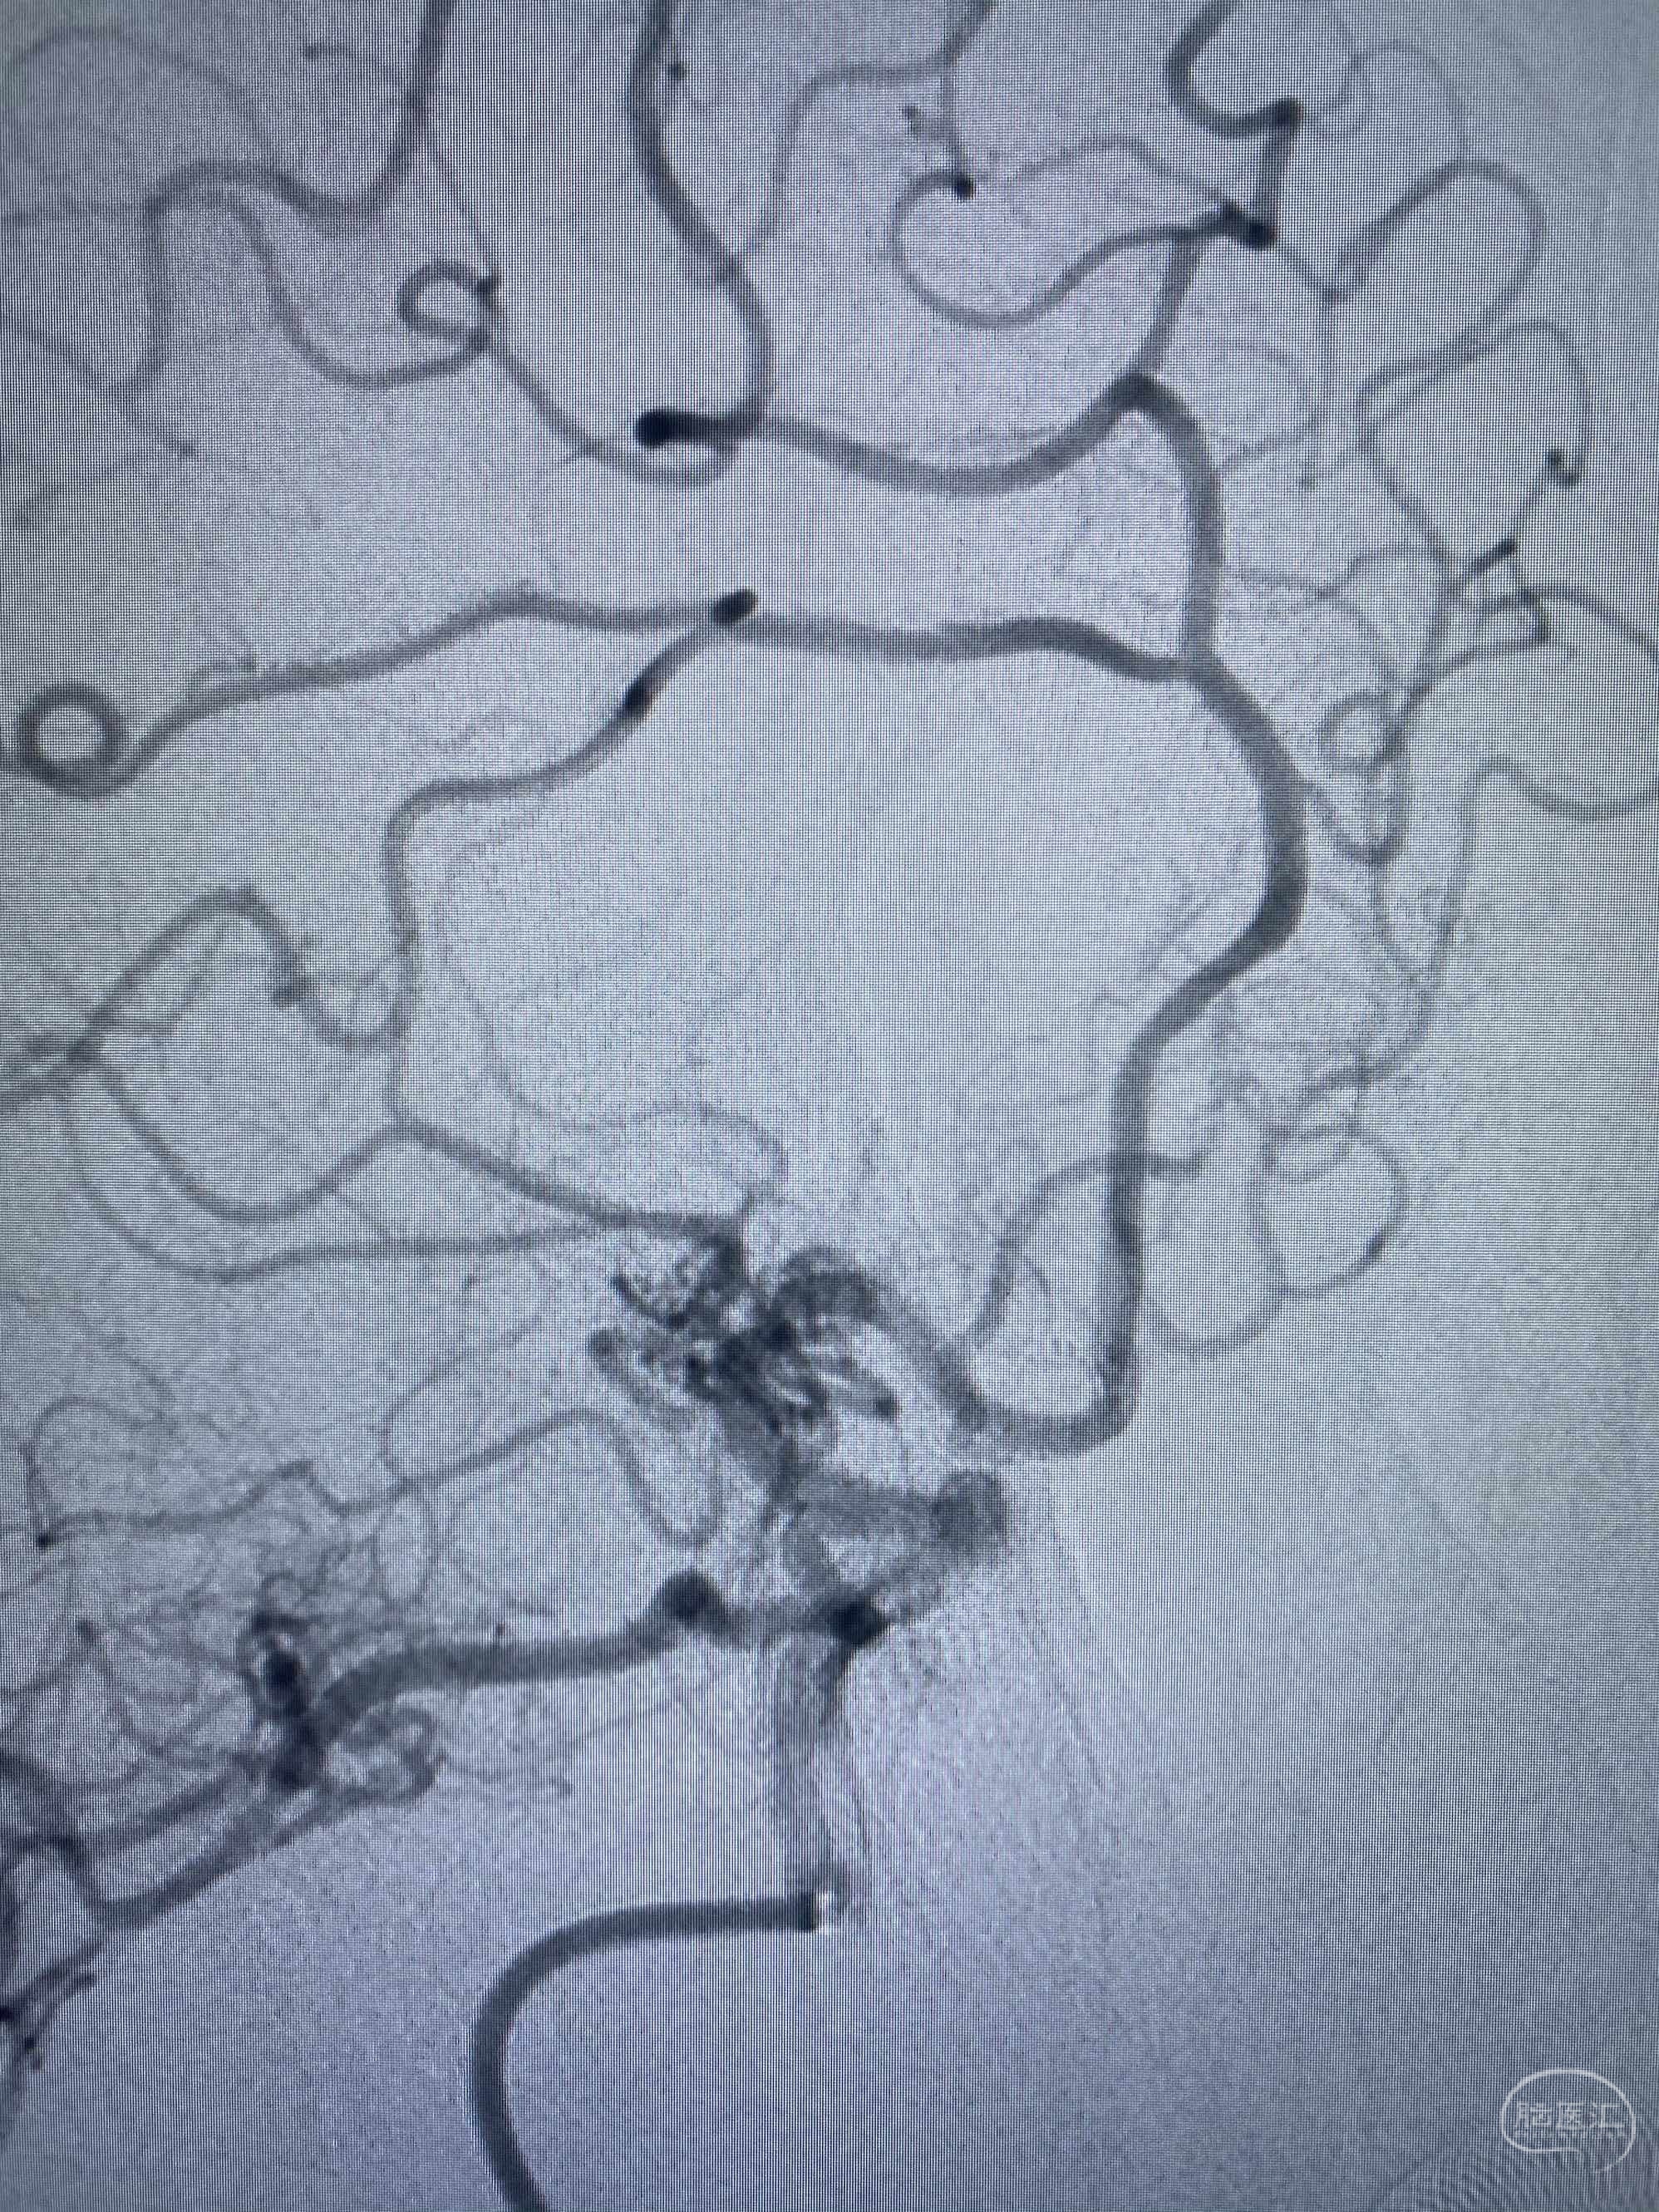

MLS,M79Y,sah,双侧MCA烟雾病,Heubner返动脉瘤,前交通段开窗,细支发出Heubner返动脉,瘤颈细长,瘤颈口比微导管细,弹簧圈2mmx3cm“隔山打牛”填塞治愈,Heubner返动脉保留。

该患者术后2天观察神志清楚,四肢活动正常。